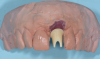

Individual anterior custom abutments should have straight or concave transmucosal profiles extending to the desired gingival line at the FMG (Figure 29 through Figure 35).

(29.) Single anterior custom abutment workflow.

Figure 29

(30.) Single anterior custom abutment workflow.

Figure 30

(31.) Single anterior custom abutment workflow.

Figure 31

(32.) Single anterior custom abutment workflow.

Figure 32

(33.) Single anterior custom abutment workflow.

Figure 33

(34.) Single anterior custom abutment workflow.

Figure 34

(35.) Single anterior custom abutment workflow.

Figure 35